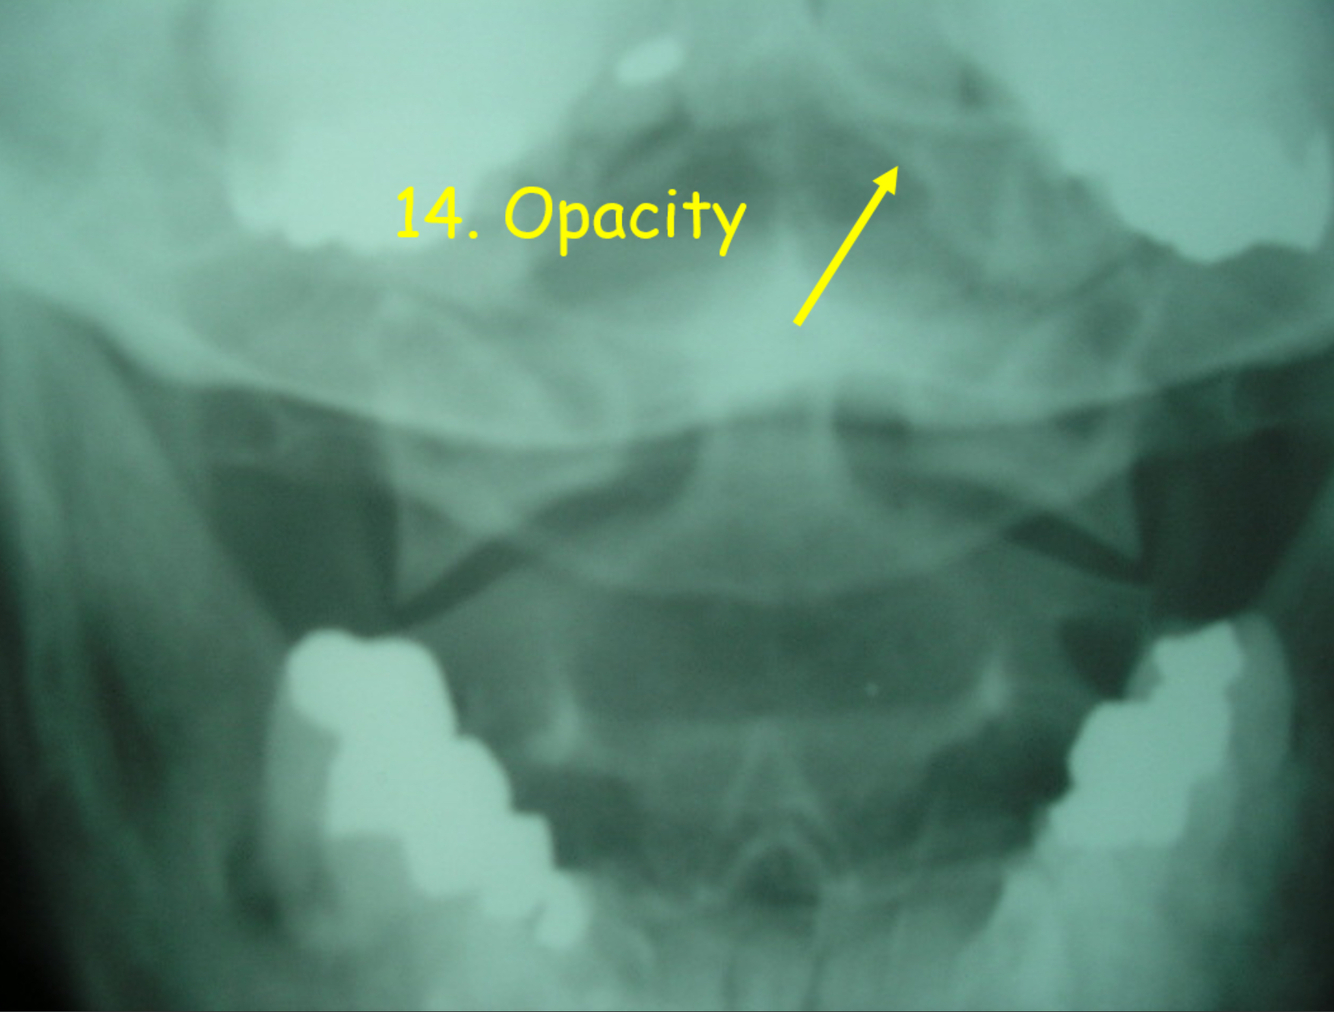

14

Q

A

nasal cavity